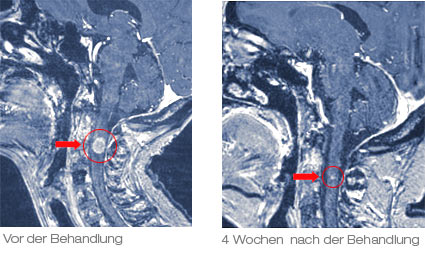

Dieses Behandlungsbeispiel zeigt den Behandlungsverlauf einer 46-jährigen Patientin mit bekannter Brustkrebserkrankung. Sie entwickelte eine lebensbedrohliche Symptomatik mit einem beginnenden Querschnittsyndrom. Die bildgebende Untersuchung der Halswirbelsäule konnte eine Metastase im oberen Teil des Rückenmarks nachweisen (linkes Bild). Es drohte eine unmittelbare Lähmung der Arme und Beine. Die Patientin wurde in unser Cyberknife Zentrum überwiesen und in einer einmaligen, 1-stündigen Sitzung behandelt.

4 Wochen nach der Behandlung war die Metastase nicht mehr nachweisbar (rechtes Bild). Die Patientin hatte eine gute Lebensqualität und konnte die Praxis wieder zu Fuß verlassen.